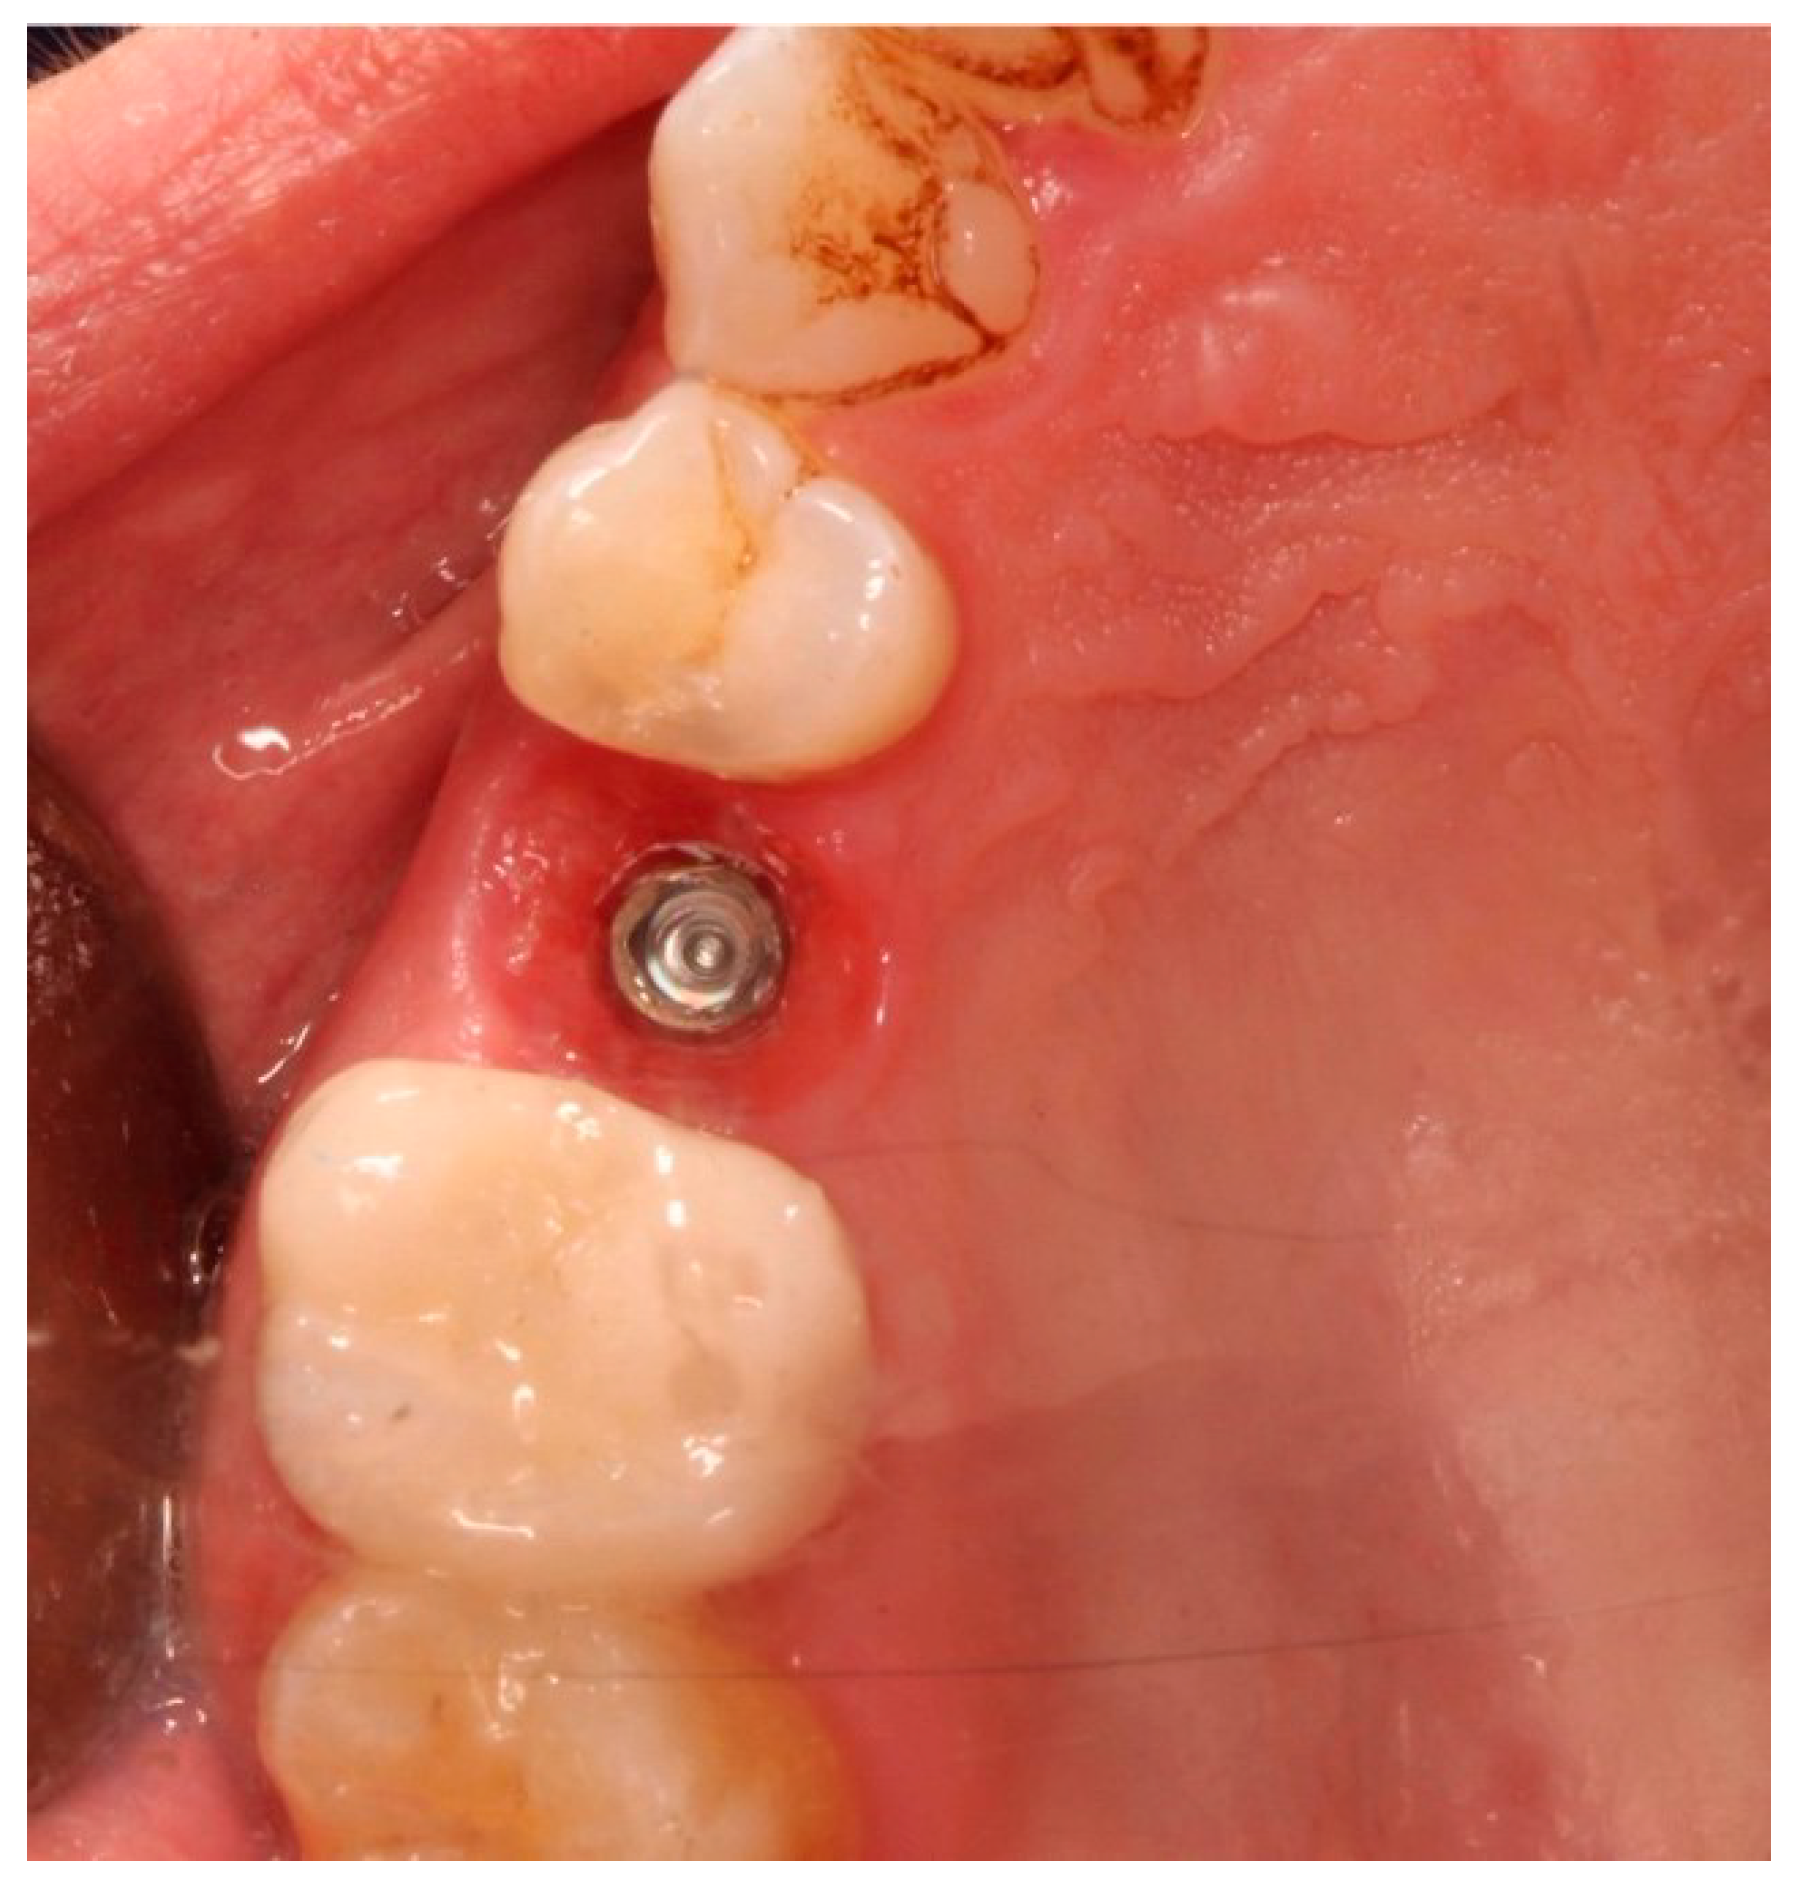

Figure 2.

Occlusal view prior to implant insertion of tooth 1.5.